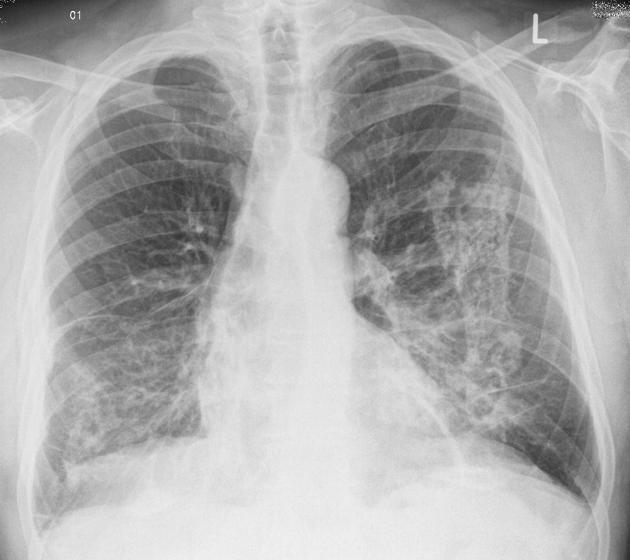

CLINICAL HISTORY:

40Yo Male

SOB for 3/12, pyrexia and cough

FINDINGS:

Bilateral asymmetrical areas of consolidation throughout both lungs, predominantly in the upper and middle zones.

No pleural abnormality is demonstrated.

Heart size is normal. The left hilum is obscured by consolidation, but the right hilum and mediastinal contours are normal.

IMPRESSION:

Appearances are suggestive of an atypical infection or inflammatory process.

BACKGROUND:

This case demonstrates eosinophilic pneumonia. Eosinophilic pneumonias represent eosinophil rich fluid filling alveolar spaces. The cause may be idiopathic, secondary to drug exposure or fungal/parasitic infection, or as part of a vasculitis (Eosinophilic granulomatosis with polyangiitis). Eosinophilic pneumonia can be further divided:

DIFFERENTIAL DIAGNOSIS:

FOLLOW-UP:

Complex pneumonias may need to assessed with HRCT

Blood tests: